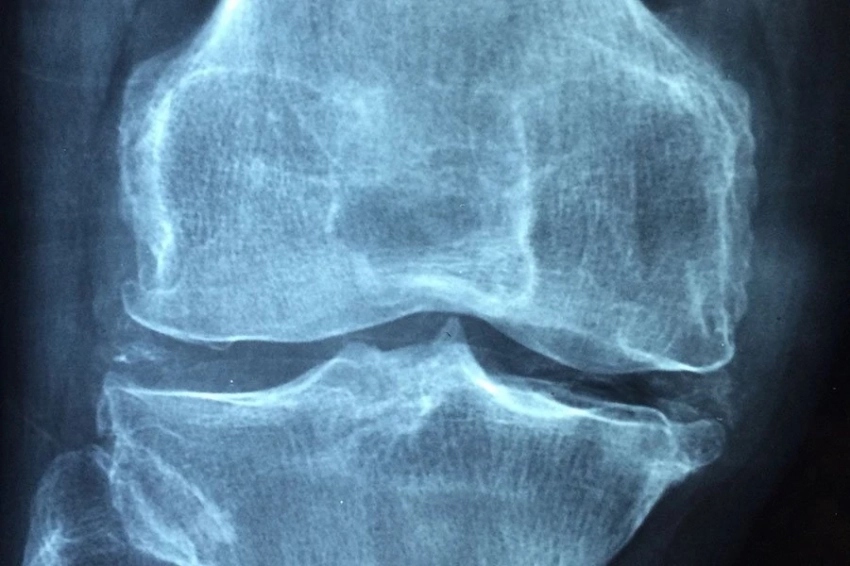

Учёные Karolinska Institutet (Швеция) обнаружили, что наличие старших братьев и сестер и удаление миндалин в детстве могут быть связаны с риском развития анкилозирующего спондилита (АС), характеризующегося воспалением суставов позвоночника, сообщается на портале BMJ.

Однако было обнаружено, что ампутация миндалин в детстве и наличие старших братьев или сестер могут быть связаны с увеличенным риском развития АС. Эти результаты были подтверждены как в случай-контрольном анализе, так и при сравнении данных братьев и сестер, что подчеркивает серьезность этих ассоциаций.